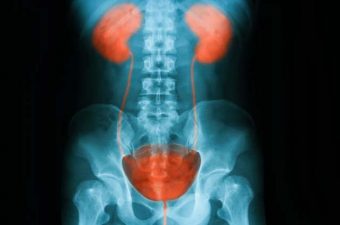

Existen tres tipos de infección urinaria:

- Cistitis: infección de la vejiga.

- Pielonefritis: infección de los riñones.

- Uretritis: infección de la uretra.

La cistitis, tema de este texto, es una inflamación de la vejiga (y también de la uretra en muchos casos) causada por una infección bacteriana. La cistitis es habitualmente una enfermedad de simple tratamiento, no obstante puede ser dolorosa e incómoda.

La infección de la vejiga puede tornarse un grave problema de salud si la bacteria se propaga hacia los riñones, lo que llamamos de pielonefritis. Mientras la cistitis es una enfermedad simple, la pielonefritis puede conducir a una sepsis y consecuentemente a la muerte por infección generalizada. En general, la pielonefritis ocurre cuando las bacterias que están en la vejiga logran subir hasta los riñones a través de los uréteres.